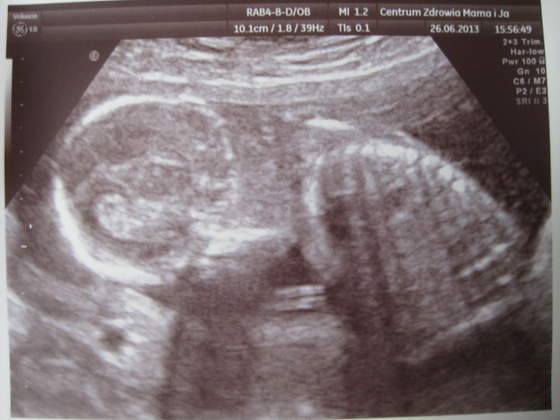

chłopaki wcześniej dają znać :-)